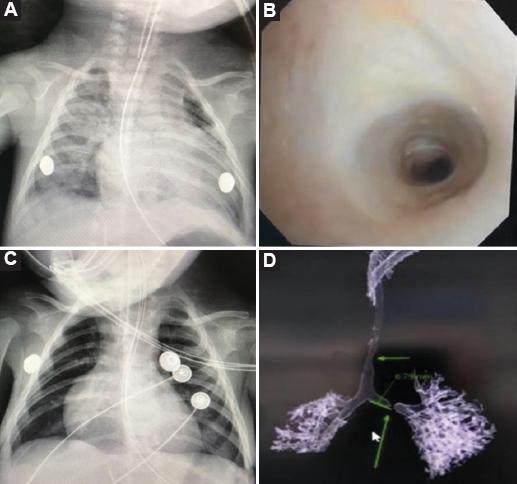

Figura 1 A: lactante con estridor y dificultad respiratoria con cánula endotraqueal (CET) de 3 mm que se detiene a nivel de la vía aérea cervical. B: presencia de estenosis crítica infundibular de anillos completos a partir del segundo anillo traqueal que confirma el diagnóstico de estenosis traqueal congénita (ETC) por broncoscopia. C: avance distal hasta la carina de una CET de 3 mm posterior a la dilatación rígida traqueal que mejora las condiciones hemodinámicas y respiratorias. D: ETC de larga extensión con colapso inspiratorio en bronquio izquierdo en una reconstrucción tomográfica de la vía aérea.

Varón de 3 meses de edad con trisomía 21 y retraso del crecimiento intrauterino, con estridor bifásico y dificultad respiratoria al nacimiento. Se logra la intubación con cánula endotraqueal (CET) de 3.5 mm que se detiene en el cuello sin lograr avanzar distal a la carina. Intubado por 1 mes y hospitalizado por 2 meses por neumonía, es egresado. Acude al servicio de urgencias con dificultad respiratoria grave y se estabiliza nuevamente con intubación endotraqueal de 3.5 mm con la punta de la CET a nivel del cuello. La ecocardiografía muestra un defecto septal atrial de 3 mm. Presenta hipertensión pulmonar de 50 mmHg y volumen espiratorio forzado del 65%, sin cardiopatías estructurales y estado de falla cardíaca secundario a un aumento en las resistencias de la vía aérea. Se realiza evaluación con broncoscopio flexible inicial de 2.8 mm, encontrando estenosis traqueal fija en el segundo anillo traqueal, extensa e infundibular de anillos completos, que no permite el paso del equipo. Se decide realizar dilatación traqueal rígida y asegurar la vía aérea con una CET de 3 mm hasta la carina. Con mejoría de las condiciones hemodinámicas, se realiza una tomografía computarizada con reconstrucción aérea que advierte estenosis traqueal larga, compleja, con colapso inspiratorio en el bronquio izquierdo. Con el paciente estable, se interviene para traqueoplastia slide (deslizamiento traqueal) a los 4 meses edad (Fig. 1).